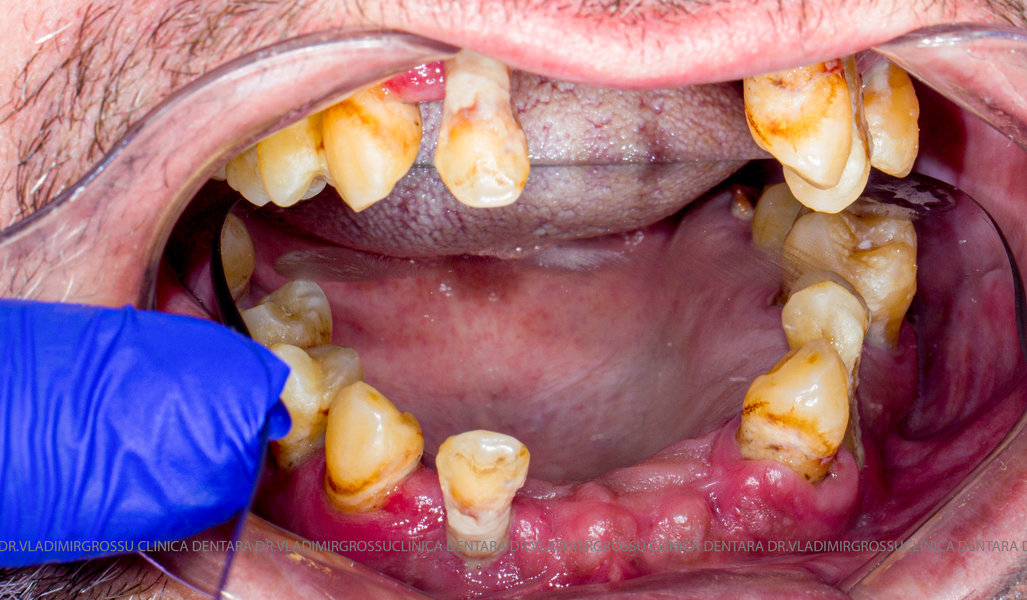

Cazuri clinice conceptul All-on-6